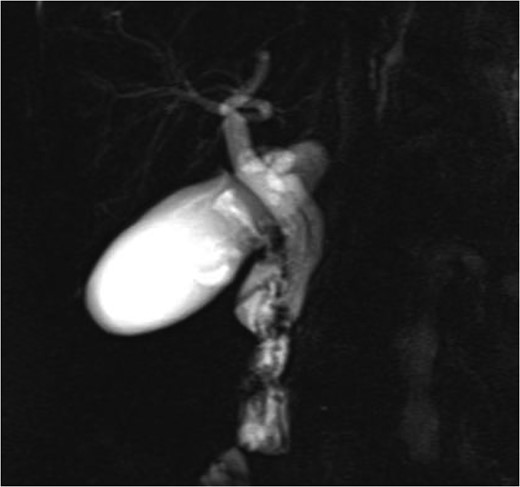

MRCP performed during the patient’s hospital stay confirmed the patient’s aberrant ductal anatomy, showing a cystic duct coursing parallel and medial to the common bile duct before anastomosing just proximal to the ampulla. CT angiogram did not show evidence of bowel ischemia.

While ultrasound and CT are able to detect dilated cystic ducts, normal cystic ducts with diameters in the range of 1–5 mm are often not detected with these modalities. MRCP is an accurate imaging modality in detecting aberrant ductal anatomy, demonstrating a cystic duct in 74% of patients [5]. Direct cholangiography, including ERCP and intraoperative cholangiography, is invasive but readily identifies anatomical variations. In this case, MRCP correctly identified the course and insertion of the cystic duct relative to the common hepatic duct (Fig. 1).

MRCP image showing long parallel course of the cystic duct inserting medially just proximal to the ampulla of Vater.